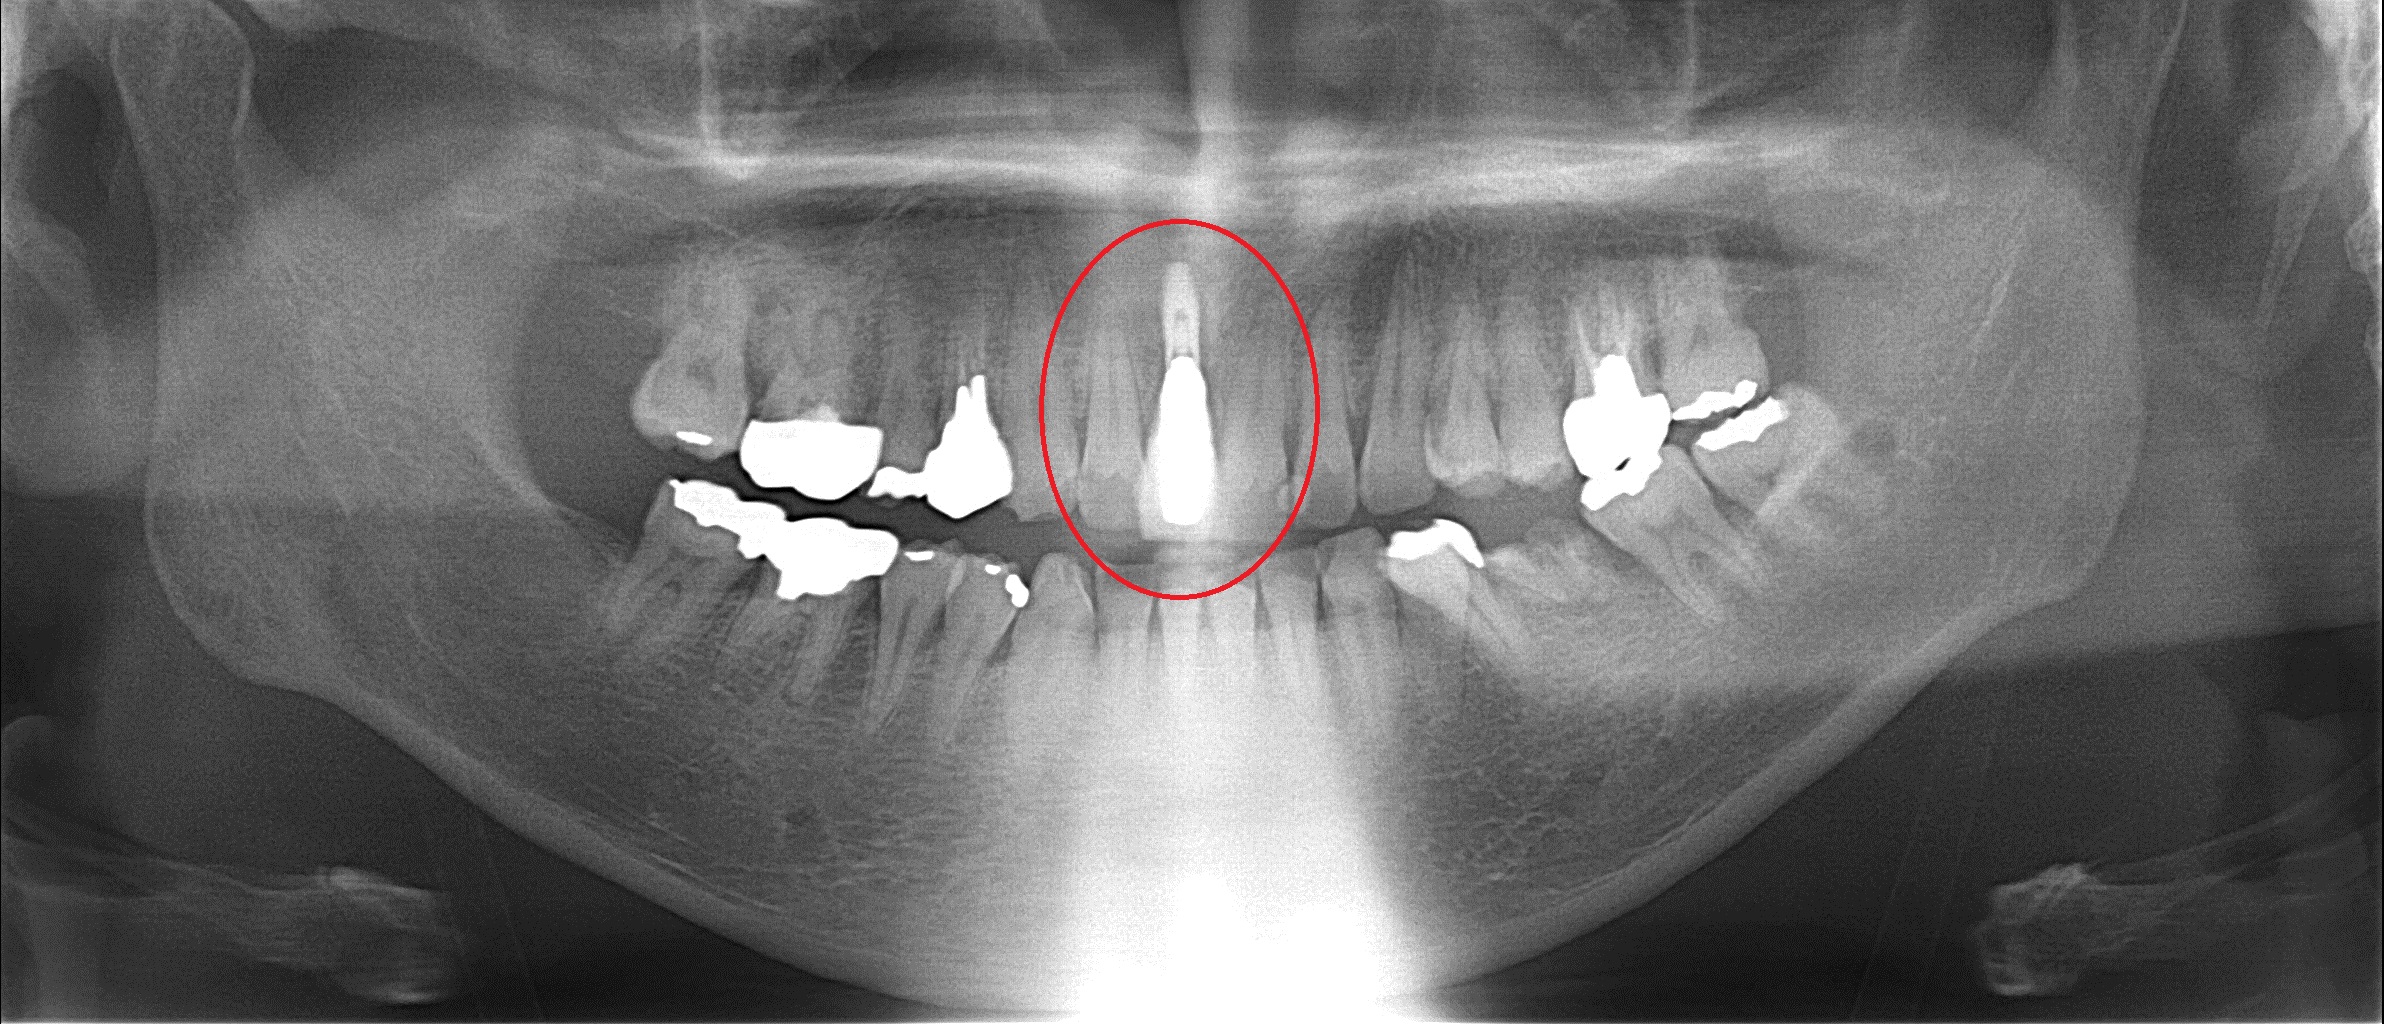

昨日の被せ物を装着後のレントゲン 赤い丸の部分にインプラントを埋入